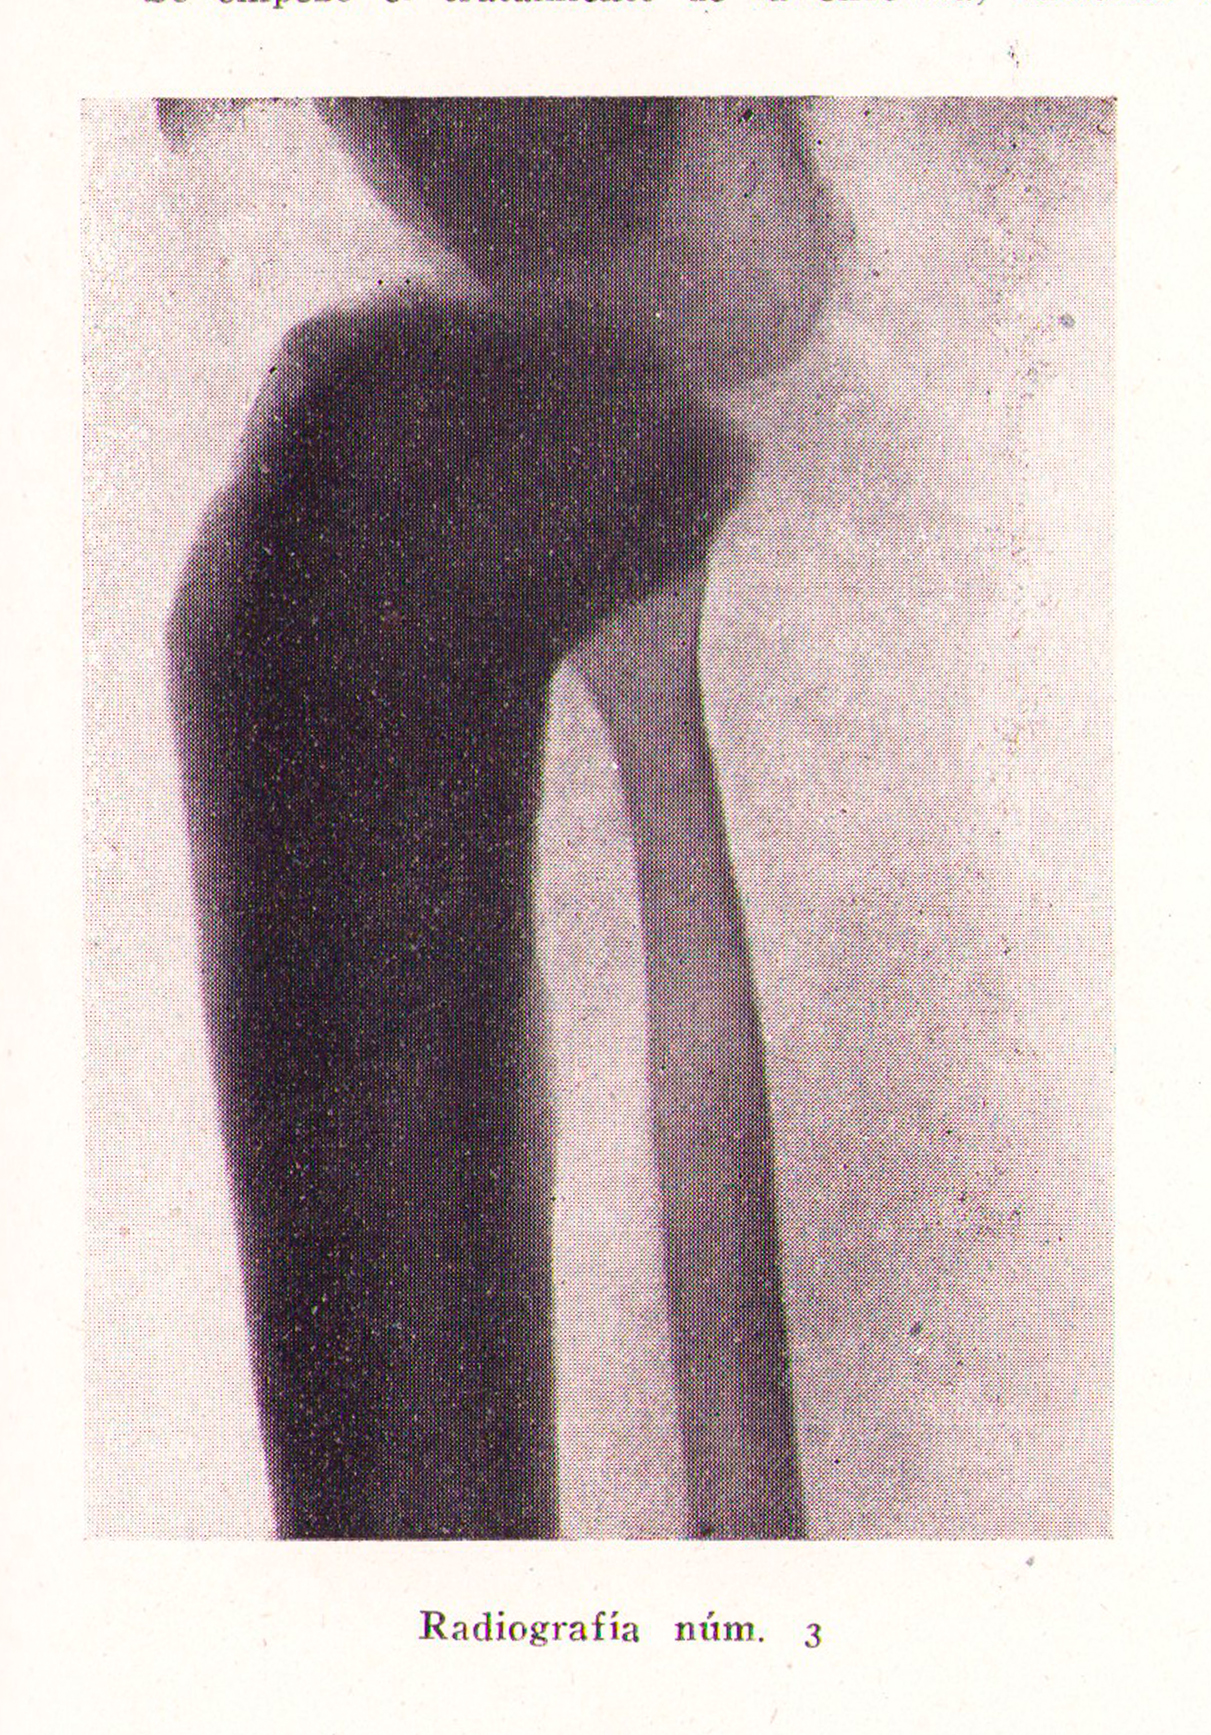

Radiografía, osteitis deformante de Paget

Revista Española de ciencias médicas, Clínica y laboratorio, Tomo XXXV, 1943